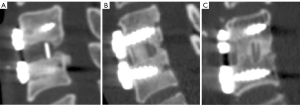

Fusion morphology classification

Based on CT 3D sagittal reconstruction, the posterior fusion bone morphology was categorized into three distinct types: stalactite shape, a fusion pattern in which bone formation occurs from both the superior and inferior endplates, curving toward the center but without complete bridging; hourglass shape, a fusion pattern in which bone bridging is achieved, but with narrowing at the center, forming a waist-like shape; and columnar shape, a fully connected and uniform-width bone bridge extending across the intervertebral space. These morphological patterns were systematically recorded at 3, 6, 12, and 24 months, and their correlation with fusion stability, intervertebral height maintenance, and subsidence risk was analyzed (Figure 2).